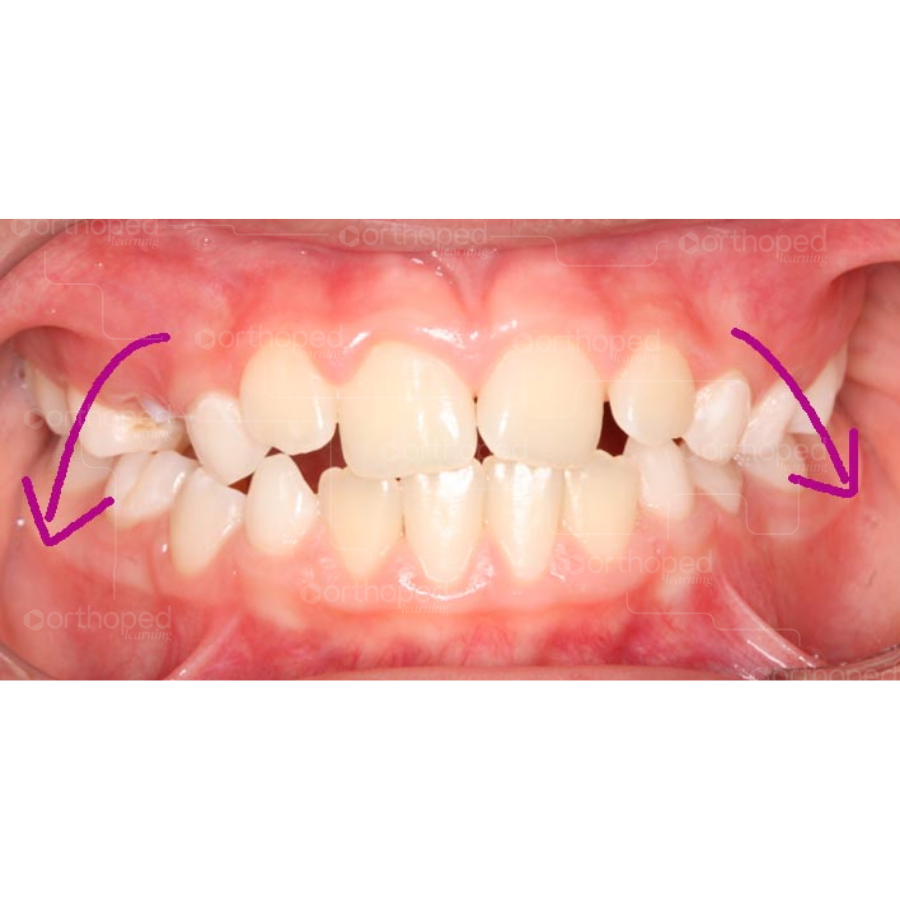

Observe abaixo a relação da borda Wala e a amplitude da maxila antes e após a expansão maxilar.

Após a expansão maxilar.